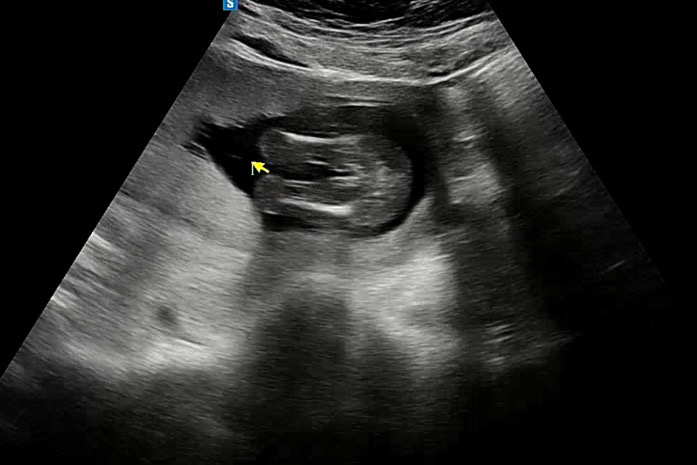

어느새 15주 3일 성별 확인을 했어요

딸이라고 하시는데 어때 보이시나요 ㅎㅎ 이정도면 성별 반전도 없는지 궁금해요 ㅎㅎ 남편이 넘 좋아해서 ^^

ㅎㅎㅎ딸이 맞는거같아여!! 저도 딸인데, 초음파사진이 비슷해용^^